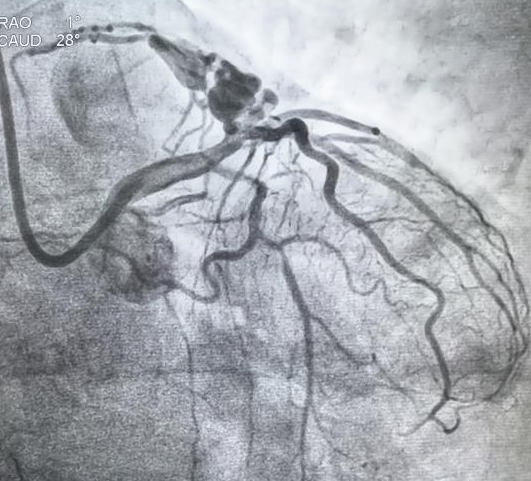

患者杨某近一年来反复有“咽部紧缩”感,多为活动诱发,休息后逐渐缓解,近2周上述症状加重并持续时间延长,严重影响生活质量。就诊我院后完善冠脉造影检查,明确为“冠状动脉-肺动脉瘘”。由我院心血管专家团队进行了充分认真的讨论准备,反复研究、充分论证,考虑该患者“心绞痛”症状与冠状动脉-肺动脉瘘有关,决定对该患者冠状动脉-肺动脉瘘封堵术。经过完善的术前准备于11月23日顺利完成冠状动脉-肺动脉瘘封堵术,术中利用特制微导管将两枚长约30mm弹簧圈置入瘤样扩张内,复查造影示冠状动脉肺动脉分流量明显减少,提示瘘管封堵成功(根据病理生理学机制,预计中远期会完全封堵)。术后该患者症状明显改善,术后第二日出院。

术前影像